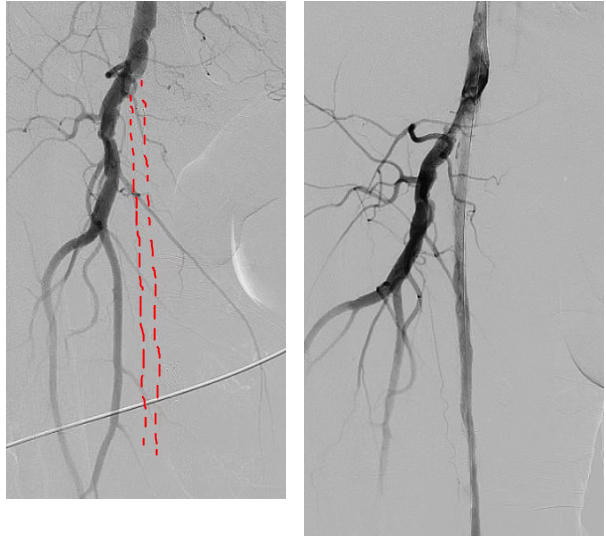

年逾七旬的张大爷,3个月前曾因“下肢动脉粥样硬化性闭塞”在某医院接受了下肢动脉支架成形术。本以为可以安心行走,可近期症状复发且持续加重。北京大学第三医院秦皇岛医院神经血管介入科团队对张大爷进行了详细的影像学检查,发现其左大腿支架内无血流信号,并且支架内血栓信号明显,这意味着张大爷的腿又“梗”住了。那些顽固的血栓斑块如同“顽固的路障”,常规治疗方案效果有限,即便暂时推开,也极易再次回弹或增生,导致血管很快再次堵塞。

面对这一棘手的局面,神经血管介入科团队经过充分的术前评估,决定为张大爷实施“下肢动脉斑块旋切术”。与传统技术不同,动脉斑块旋切系统就像一台精准的“血管清道夫”,能通过微小的穿刺口,将特制的旋切导管送至血管堵塞处,直接、精准地将堵塞血管的斑块粉碎并取出,而非仅仅是挤压。这种技术能从根源上清除堵塞物,减少血管内膜的损伤,降低了术后再狭窄的发生率。

手术医生在成功完成斑块旋切后,又辅以“下肢动脉球囊扩张成形术”,对局部残余狭窄进行优化塑形。术后,张大爷下肢血流立即得到改善,下肢皮温转暖,疼痛感消失。次日复查显示,下肢动脉血流通畅,管腔形态良好,2日后康复出院。